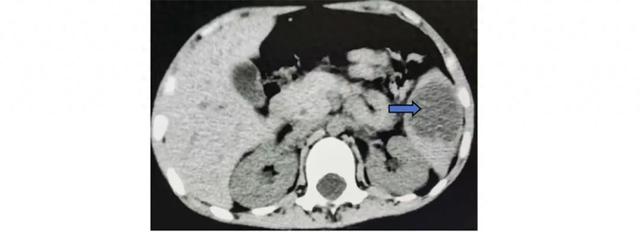

血培养、大便培养、结核菌素试验、G试验、GM试验均阴性。腹部超声提示,脾脏下部存在异常回声区,类圆球形,边界可见范围约5.2 cm × 4.4 cm × 3.3 cm,超声引导穿刺抽脓,脓液菌培养阴性。

回顾这个病例,具有以下特点:(1)影像学显示深部脓肿;(2)抽吸标本的病原学检查阴性;(3)抗生素治疗无效,常规抗生素治疗持续2周,抗结核治疗3个月;(4)糖皮质激素治疗后临床改善,1个月激素治疗后影像学改善。临床诊断:脾无菌性脓肿。白塞病中分泌白介素18的T细胞的异常免疫反应可引起在中性粒细胞浸润。因此,T细胞介导的异常免疫反应可解释肝脾等的无菌性脓肿表现。